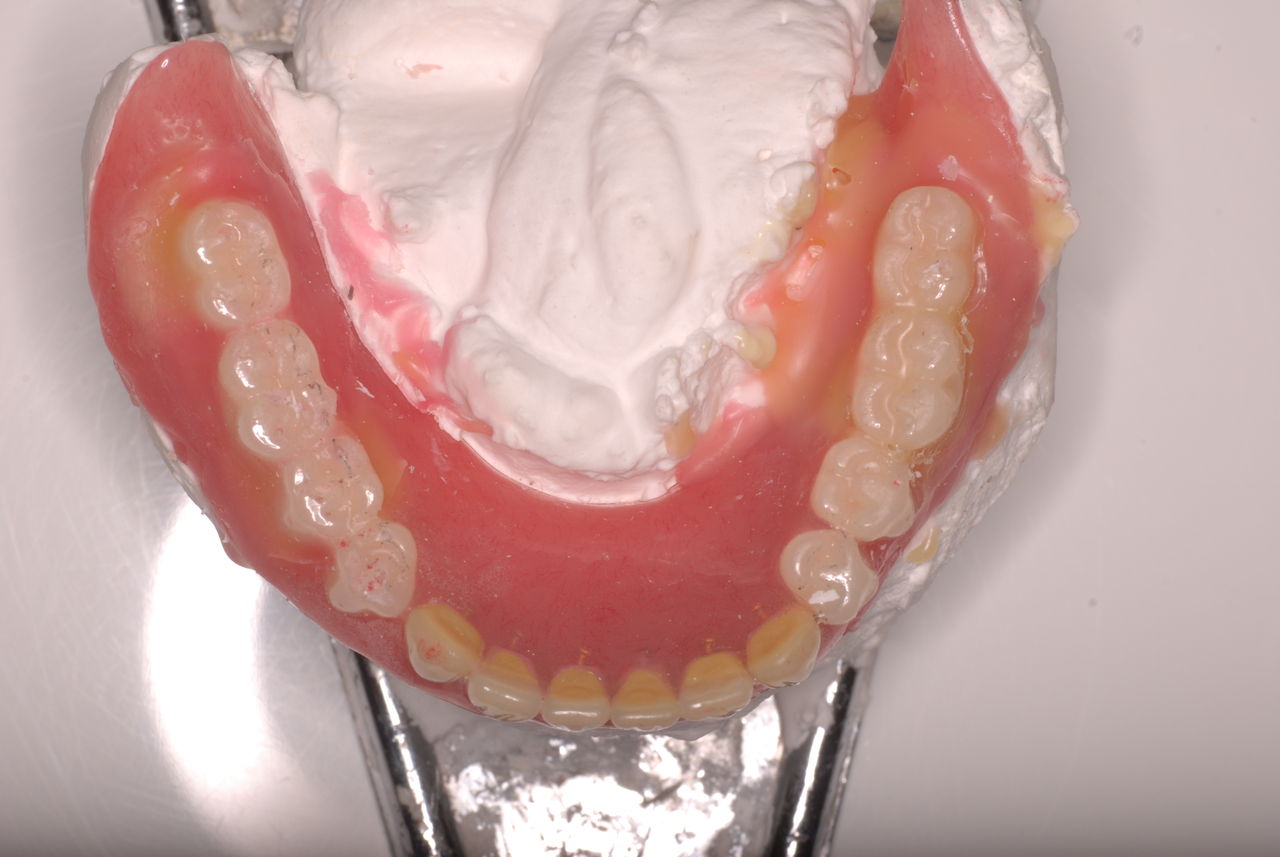

クラスプという歯を取り囲むワイヤ−が折れたりしてまともに機能していません。構造的な問題もあるのでしょうがヒビも目立ちます。殆ど使わずに御蔵入りとなったようです。値段の問題からかそうではないか判然としませんが、入れ歯というのは残りの歯や歯周病の治療がある程度完了してからでないと良い機能的な入れ歯などはできません。せいぜい治療中用の簡素な物を作成して歯や歯茎の病気が治るのを待ちながら様子をみるしかないのです。